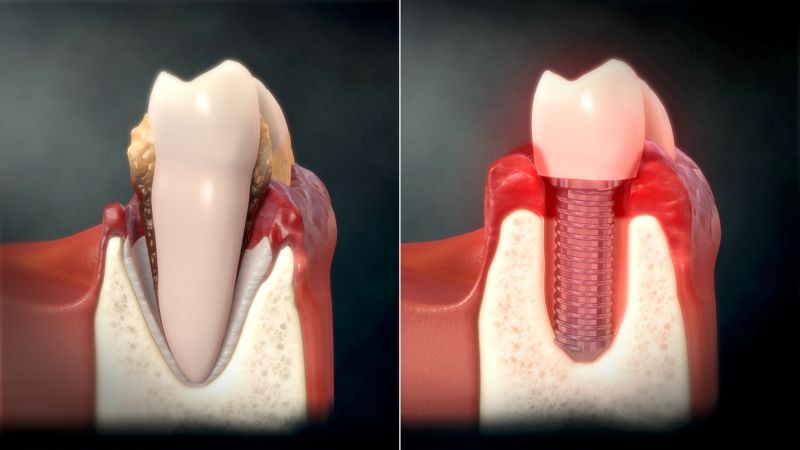

임플란트란 소실된 치아 자리에 티타늄 나사못을 심고 보철물을 얹어 치아 기능을 회복시키는 치료법이다. 임플란트는 금속 소재이기 때문에 충치가 생기지는 않는다고 알려졌지만 그렇다고 해서 문제가 없는 것은 아니다. 치주염이 생기듯 임플란트 주위 잇몸에 염증이 발생할 수 있기 때문이다. 임플란트 주위 잇몸에 염증이 발생하면 구취, 출혈을 유발하고 잇몸과 치조골의 손상을 불러오는데 이를 임플란트 주위염이라고 한다.

그렇다면 왜 임플란트 주위염은 치주염보다 더 무서운 속도로 잇몸과 뼈를 손상시키는 것일까? 임플란트의 구조적 특징과 자연치아와의 차이 등을 명쾌하게 알아본다.